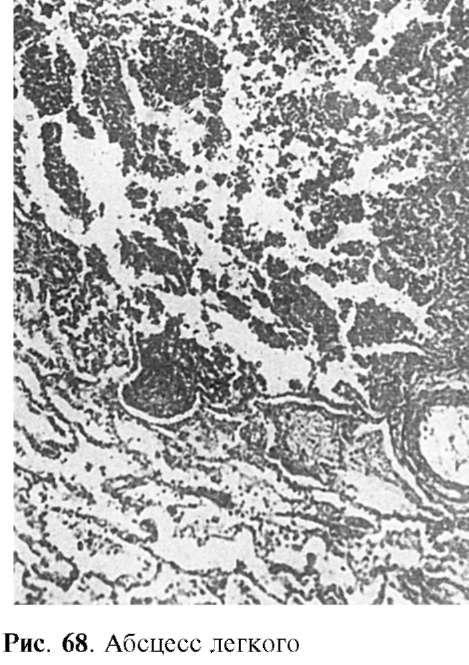

Абсцесс (гнойник) - очаговое гнойное воспаление, характеризующееся образованием полости, заполненной гноем (рис. 68). Гнойник со временем отграничивается валом грануляционной ткани, богатой капиллярами, через стенки которых происходит усиленная эмиграция лейкоцитов. Образуется как бы оболочка абсцесса. Снаружи она состоит из соединительнотканных волокон, которые прилежат к неизмененной ткани, а внутри - из

грануляционной ткани и гноя, непрерывно обновляющегося благодаря выделению грануляциями гнойных телец. Оболочку абсцесса, продуцирующую гной, называют пиогенной мембраной.